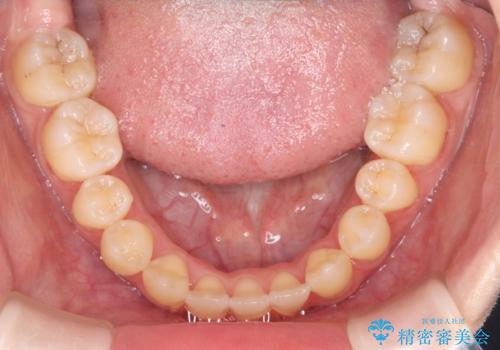

診査の結果、すでに下顎前歯の抜歯が行われていましたが、マウスピースの適合が著しく悪くなっており、歯が計画通りに動いていない状態でした。また、歯を支える骨の厚みや歯肉の薄さを考慮すると、このままマウスピースによる傾斜移動を続けるのは歯肉退縮(歯茎が下がること)のリスクが非常に高いと判断。